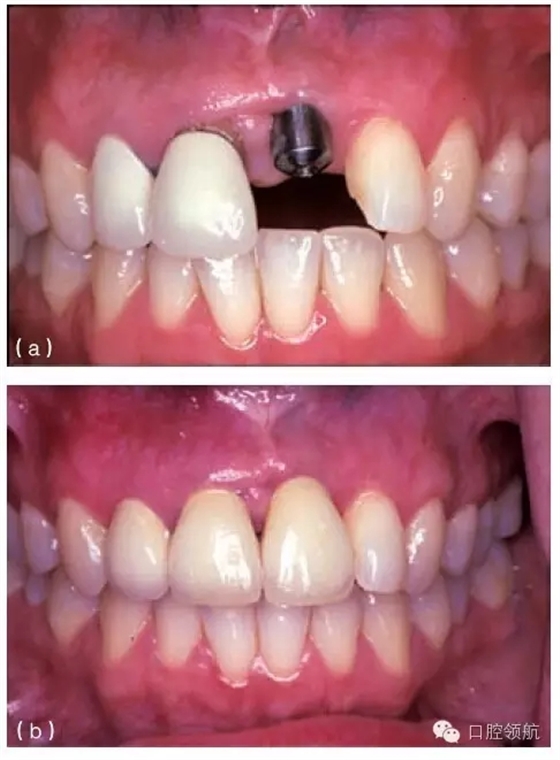

其他的美學(xué)問(wèn)題與種植體植入位置不當(dāng)(圖10.20a,b),以及植入前存在骨吸收有關(guān)。骨吸收的存在使種植體無(wú)法植入到理想位置,造成單冠之間或是固定局部義齒的橋體之間存在頸部間隙(圖10.21)。

圖10.20 (a)中切牙種植體的位置太偏唇側(cè),采用定制的基臺(tái)盡可能補(bǔ)償頰側(cè)的錯(cuò)位。(b)一并更換相鄰的兩個(gè)冠修復(fù)體以獲得更滿意的結(jié)果。

種植體植入太偏唇側(cè),將造成明顯的美學(xué)問(wèn)題,而且通常很難克服(圖10.20a,b)。